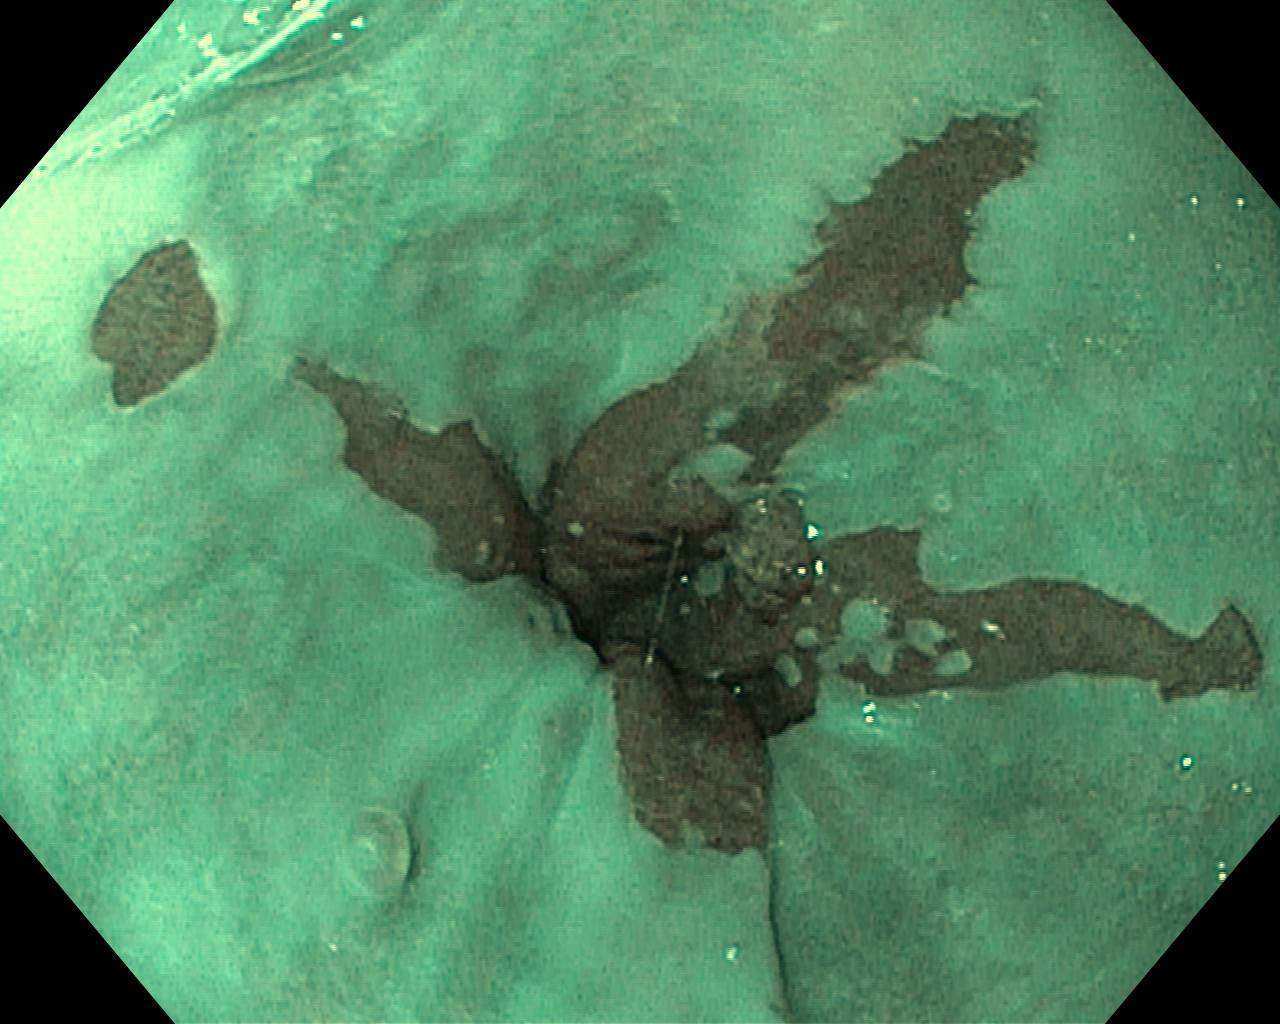

Przełyk Barretta